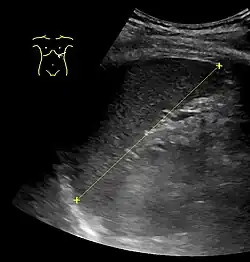

Measurements

90% reference range (5th to 95th percentile) of spleen length by abdominal ultrasonography by height of the person[11]

Height Spleen length

Women Men

155–159 cm 6.4–12 cm

160–164 cm 7.4–12.2 cm 8.9–11.3 cm

165–169 cm 7.5–11.9 cm 8.5–12.5 cm

170–174 cm 8.3–13.0 cm 8.6–13.1 cm

175–179 cm 8.1–12.3 cm 8.6–13.4 cm

180–184 cm 9.3–13.4 cm

185–189 cm 9.3–13.6 cm

190–194 cm 9.7–14.3 cm

195–199 cm 10.2–14.4 cm

The spleen, in healthy adult humans, is approximately 7 to 14 centimetres (3 to 5+12 in) in length. It weighs between 1 oz (28 g) and 8 oz (230 g) (standard reference range),[12] correlating mainly to height, body weight and degree of acute congestion but not to sex or age.[13]

Calculators have been developed for measurements of spleen size based on CT, US, and MRI findings.